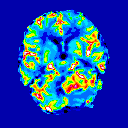

‘Measuring blood flow in childhood brain tumours using magnetic resonance imaging’ Stephanie Withey

My research involves measuring blood flow in childhood brain tumours using magnetic resonance imaging (MRI). While patients are having their scan they are given an injection of a dye which enters the brain tumour and changes how it looks on the pictures from the MRI. I write computer programs that use these changes to give us extra information on the type of tumour it is and how well the treatment is working.